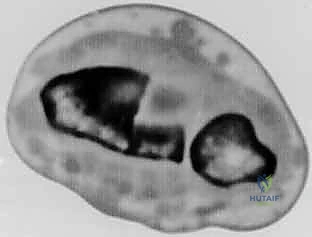

- الأشعة المقطعية (CT Scan) مع إعادة البناء ثلاثي الأبعاد (3D Reconstruction): هذه الخطوة حاسمة. تتيح للدكتور هطيف رؤية العظم من جميع الزوايا، وتحديد مكان القص بدقة متناهية.

بناءً على التخطيط الثلاثي الأبعاد المسبق، يستخدم الدكتور هطيف مناشير عظمية دقيقة جداً لعمل شق في العظم في نقطة التشوه الأصلية. يتم فتح العظم وتعديل زاويته واستعادة طوله الطبيعي.